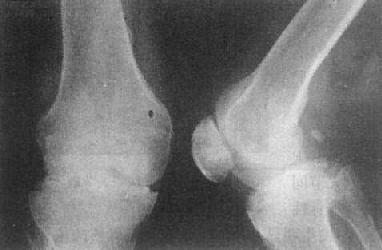

(三)关节退行性变 关节退行性变(degeneration lf joint)早期改变开始于软骨,为缓慢发生软骨变性、坏死和溶解,骨板被吸收并逐渐为纤维组织或纤维软骨所代替,广泛软骨坏死可引起关节间隙狭窄。继而造成骨性关节面骨质增生硬化,并于骨缘形成骨赘。关节囊肥厚、韧带骨化。

关节退行性变的早期X线表现主要是骨性关节面模糊、中断、消失。中晚期表现为关节间隙狭窄、软骨下骨质囊变和骨性关节面边缘骨赘形成,不发生明显骨质破坏,一般无骨质疏松。

这种变化多见于老年,以承受体重的脊柱和髋、膝关节为明显(图2-1-15、16),是组织衰退的表现。此外,也常见于运动员和搬运工人,由于慢性创伤和长期承重所致。不少职业病地方病可引起继发性关节退行性变。

关节退行性变-膝关节退行性骨关节病

图2-1-16 关节退行性变-膝关节退行性骨关节病

膝关节的关节间隙变窄,边角锐利,有骨赘形成,关节面平而致密